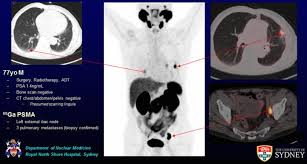

St Paul Hospital Pet Scan : Pet scans are usually carried out on an outpatient basis.

St Paul Hospital Pet Scan : Pet scans are usually carried out on an outpatient basis.. St paul pet hospital is owned by st paul resident dr. Owned by emmanuel care, st. By helping one another, we make our city a better place. The table may be hard or cold, but you can request a blanket or pillow. Before my pet/ct scan procedure, i had to answer several questions.

Pet ct scan prices depend on the hospital. It involves an injection with a tracer that allows us to see how organs and tissues are working. Paul's hospital is an acute care teaching and applied research hospital delivering compassionate and holistic care to the people of saskatoon and saskatchewan. An intercom in the room allows you to speak to someone at any time. The table may be hard or cold, but you can request a blanket or pillow. I am very happy for you paul that your pet scan came out with positive results. Available to ubc students and hospital employees. A pet scan causes no pain. This means you won't need to stay in hospital overnight. Inspired by the example of st. Friday, march 29th st paul pet hospital cathedral hill will be closing at 5:30pm due to staff meeting purposes. Paul pet hospital is one of the best animal hospitals in the twin cities. Compare pricing for medical facilities in st.